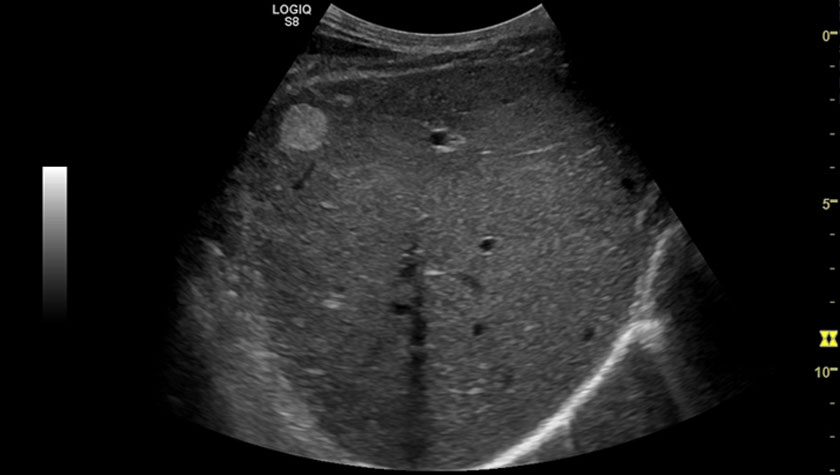

Печень, датчик C1-6-D

Печень, датчик C2-9-D

Печень, УЗИ с контрастами (CEUS), датчик 9L-D